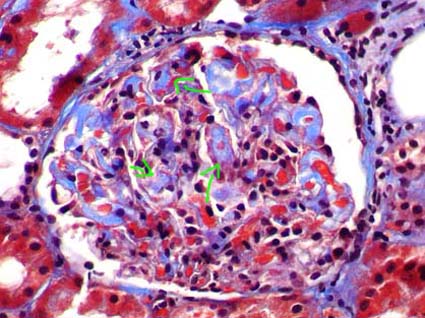

The commonest lesion is glomerulonephritis (GN) with morphologic aspects similar to type I membranoproliferativa GN (MPGN). Glomerular hypercellularity is predominantly by leukocytes and monocytes (different to idiopathic MPGN in which hypercellularity is mainly by mesangial and endothelial cells). Capillary walls show similar characteristics to those of idiopathic MPGN: double contours, “tram-tracking” aspect, duplication of the GBM and cells interposition in the subendotelial space (mainly monocytes) (Figure 12). Usually there are nodular, eosinophilic, hyaline, homogeneous deposits occupying some glomerular capillary lumina: intraluminal thrombi; when they are seen they are very suggestive of the disease (Figure 13). Crescents are not frequent and if present it is usually mild and in few glomeruli. In few patients there is mesangial hypercellularity and sclerosis, often associated to severe proteinuria and progression to chronic renal damage.

Figure 12. Glomerulus with notorious increase of size, nodular aspect, and thickening of capillary walls. With the other stains a MPGN aspect was demonstrated. In addition, there are intraluminal thrombi (see Figure 13). Patient with type II mixed cryoglobulinemia. (Masson’s trichrome, X400).

Figure 13. Same case of the Figure 12. The arrows indicate intracapillary hyaline thrombi; these are very characteristic of renal involvement in cryoglobulinemia. These “thrombi” are positive for immunoglobulins (in this case for IgG and IgM). (Masson’s trichrome, X600).